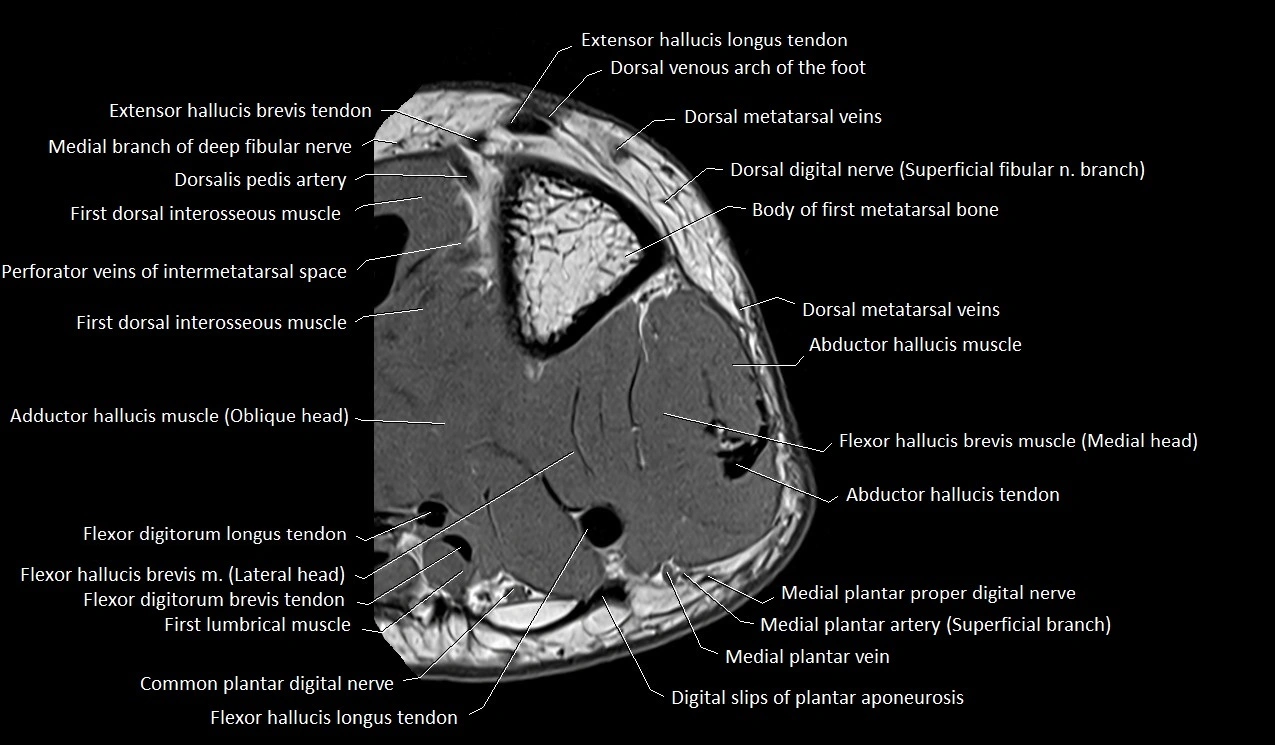

MRI image

image